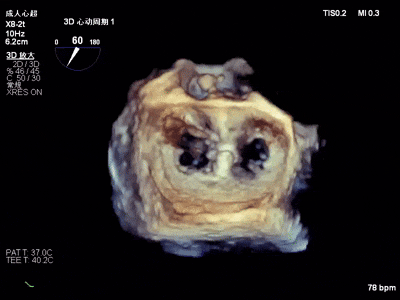

术前心超

退行性二尖瓣反流(DMR),P1/P2交界脱垂连枷(脱垂范围7mm,连枷间距4mm)

新分型:AAA型,MR 4+,VC:4×7mm

A1.5:20mm,P1.5:10mm,AP:30mm,MVA约3.8cm²

术中超声要点